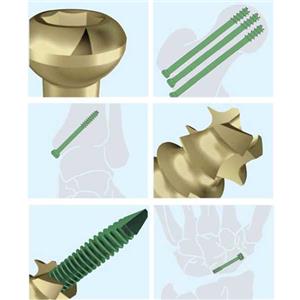

لوحة العظام الجراحية لزرع سبائك التيتانيوم في جسم الإنسان

غالبًا ما تستخدم صفائح العظام الجراحية المزروعة من سبائك التيتانيوم لعلاج كسور العظام أو التشوهات في جسم الإنسان. التيتانيوم معدن قوي وخفيف الوزن متوافق حيوياً ، مما يعني أنه لا يسبب أي ردود فعل سلبية أو رفض من قبل الجهاز المناعي للجسم.